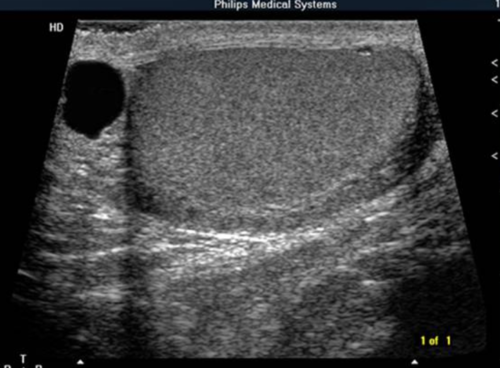

THIS IMAGE REPRESENTS WHICH OF THE FOLLOWING:

transverse image of the testicle

sagittal image of the testicle

transverse image of the testicle with a hydrocele

sagittal image of the testicle with an epididymal cyst